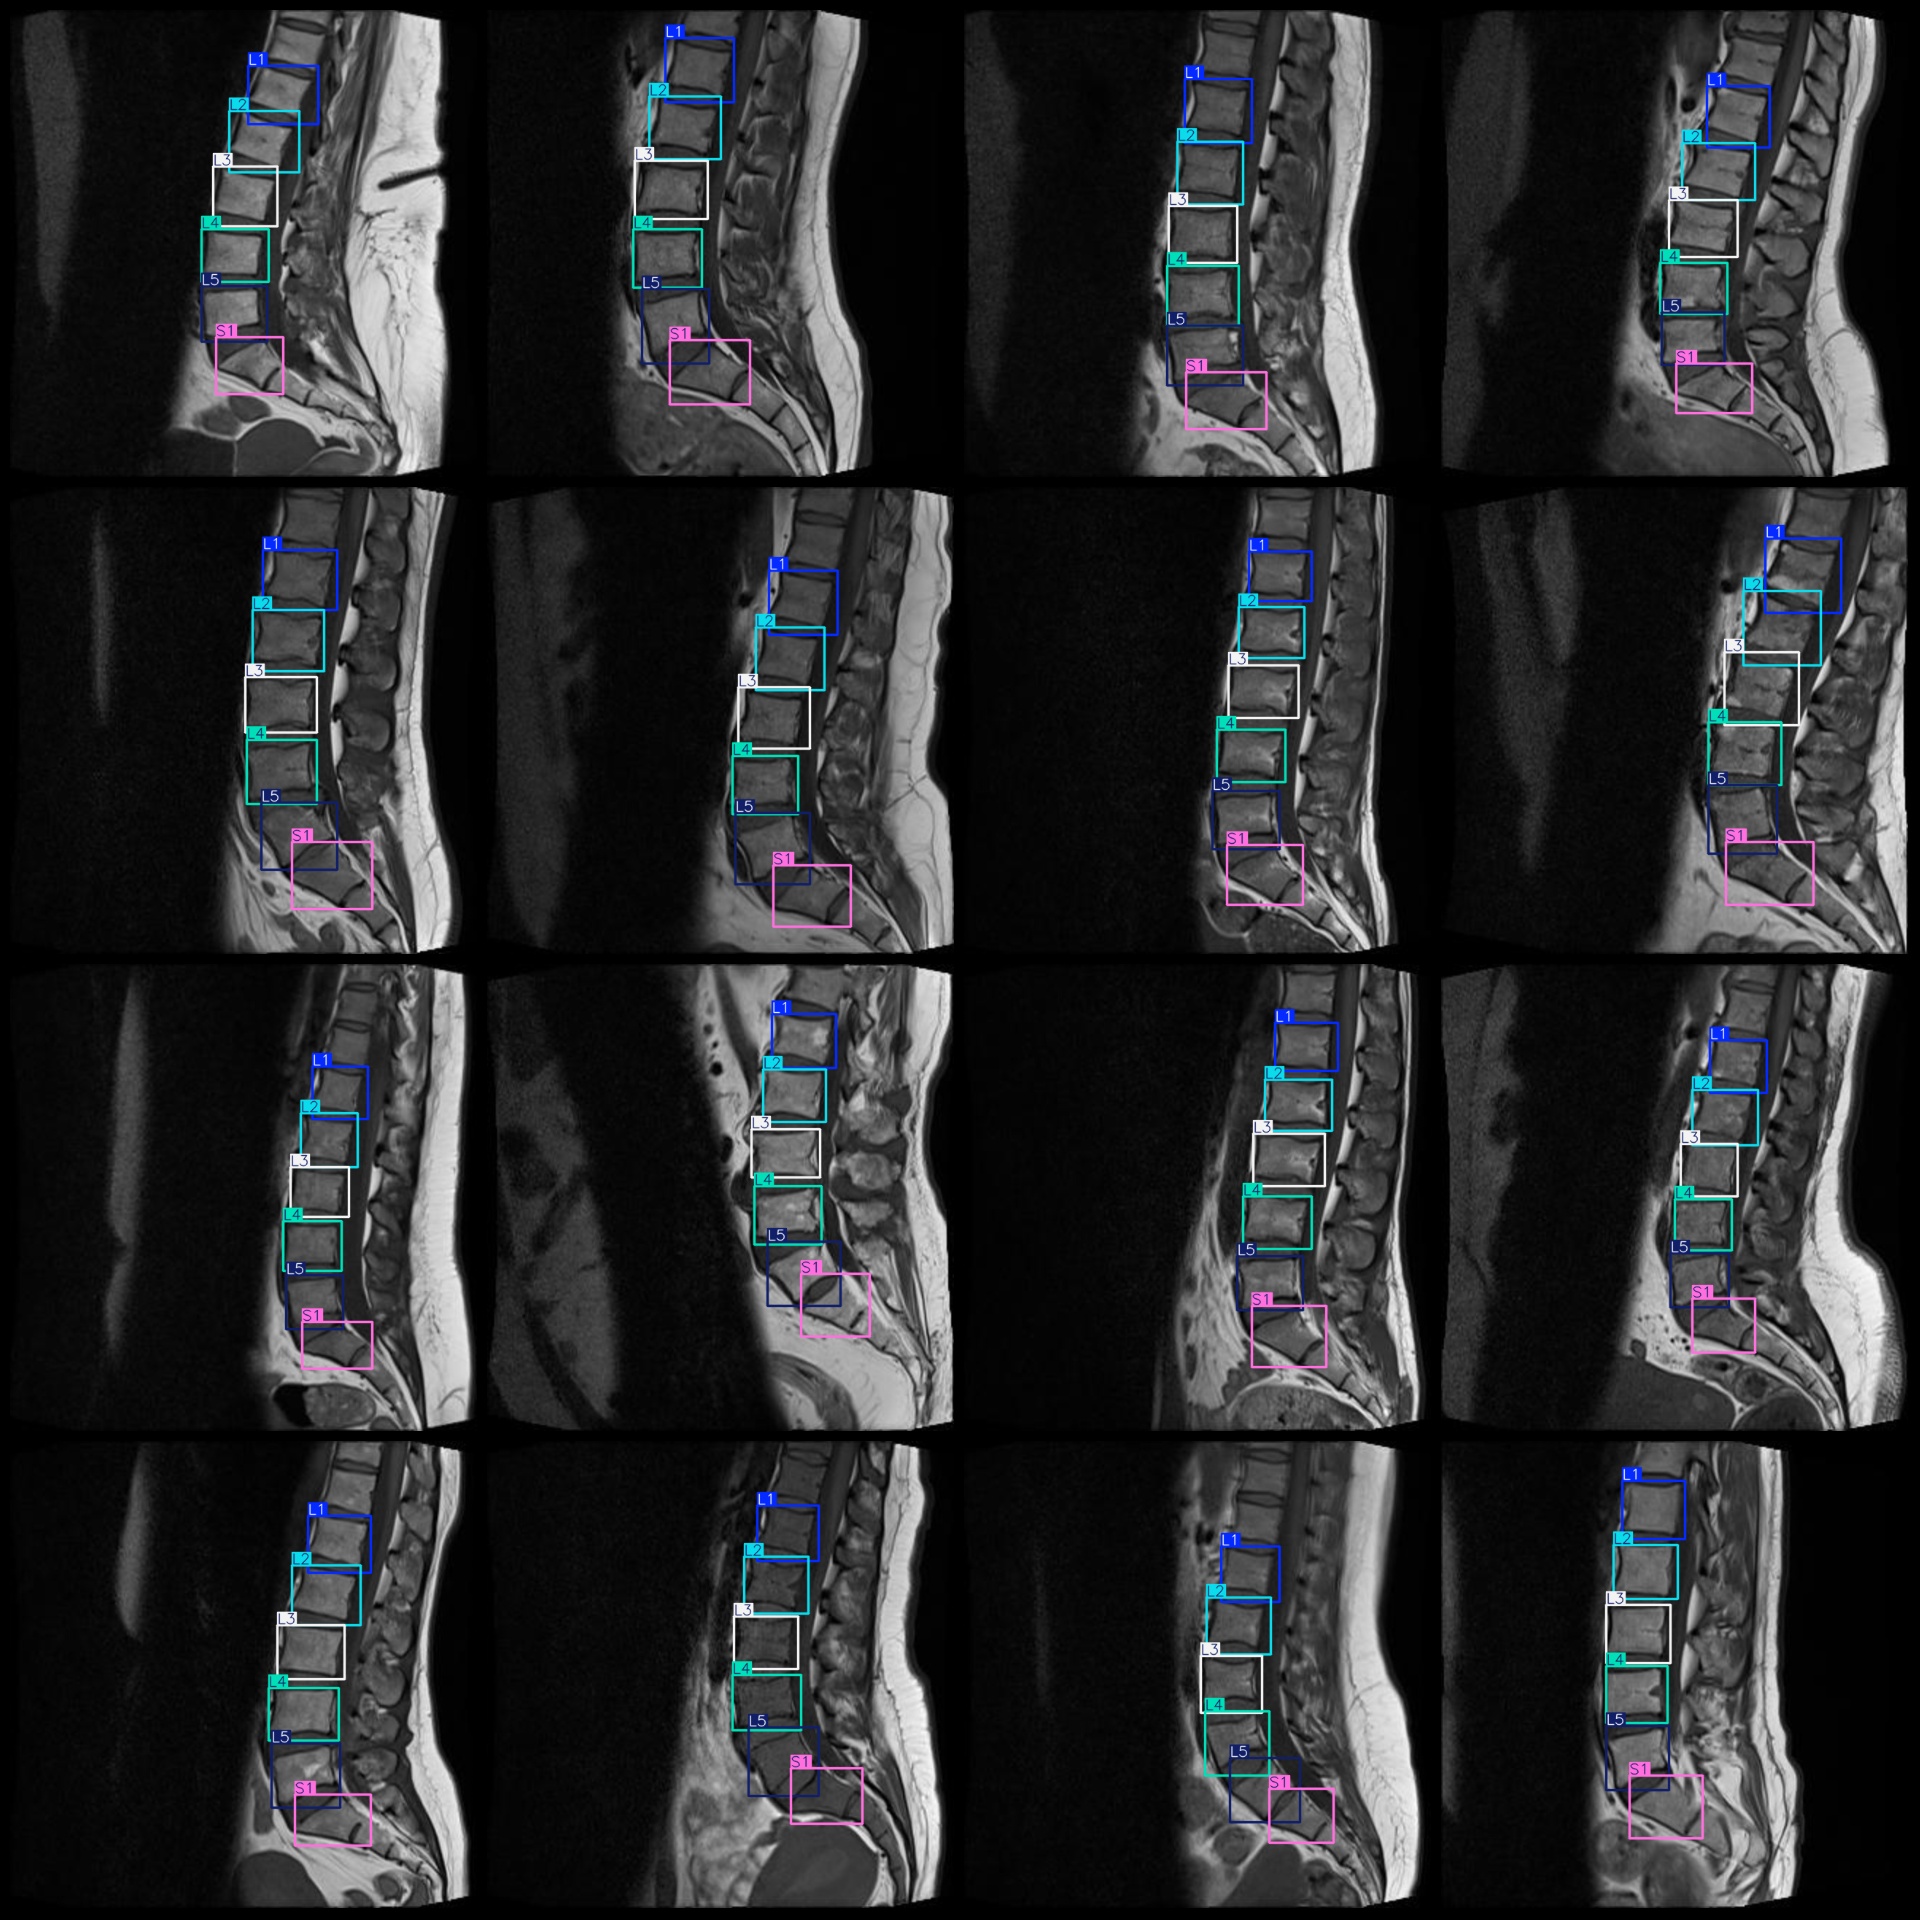

图片预览:

标注例子:

标注类别名称(注意yolo格式类别顺序不和这个对应,而以labels文件夹classes.txt为准):["L1","L2","L3","L4","L5","S1"]

标注类别数:6

标注规则:对类别进行画矩形框